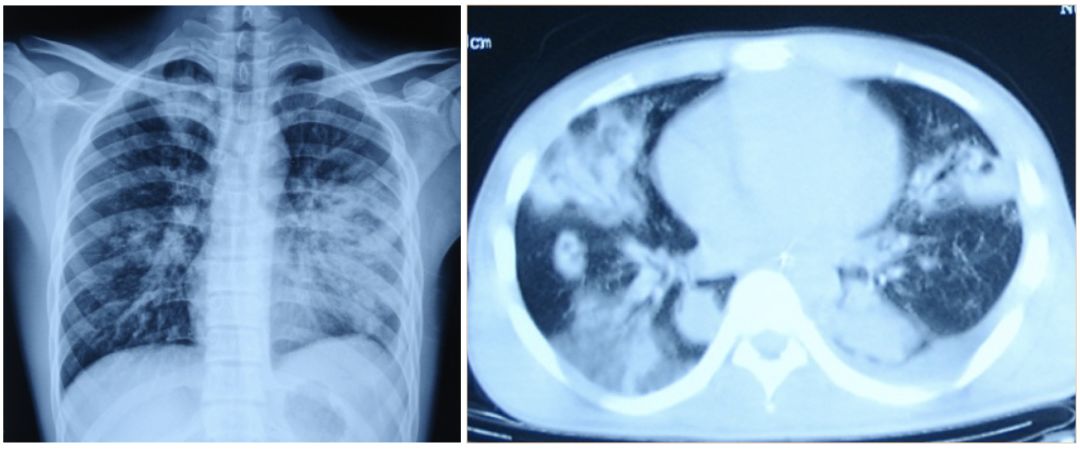

• 流感病毒肺炎的影像学

胸部X线特征性的改变是肺部出现磨玻璃样、线状或网状等间质性阴影,可累及双肺【图1】;一般没有所谓的浸润或实变影,也不会出现空洞。组织病理表现为弥漫性肺泡损伤(DAD),极少数的患者可以表现为闭塞性细支气管伴机化性肺炎(BOOP),此时可出现胸膜下的肺部实变【图2】

图1                                                                                                                图2